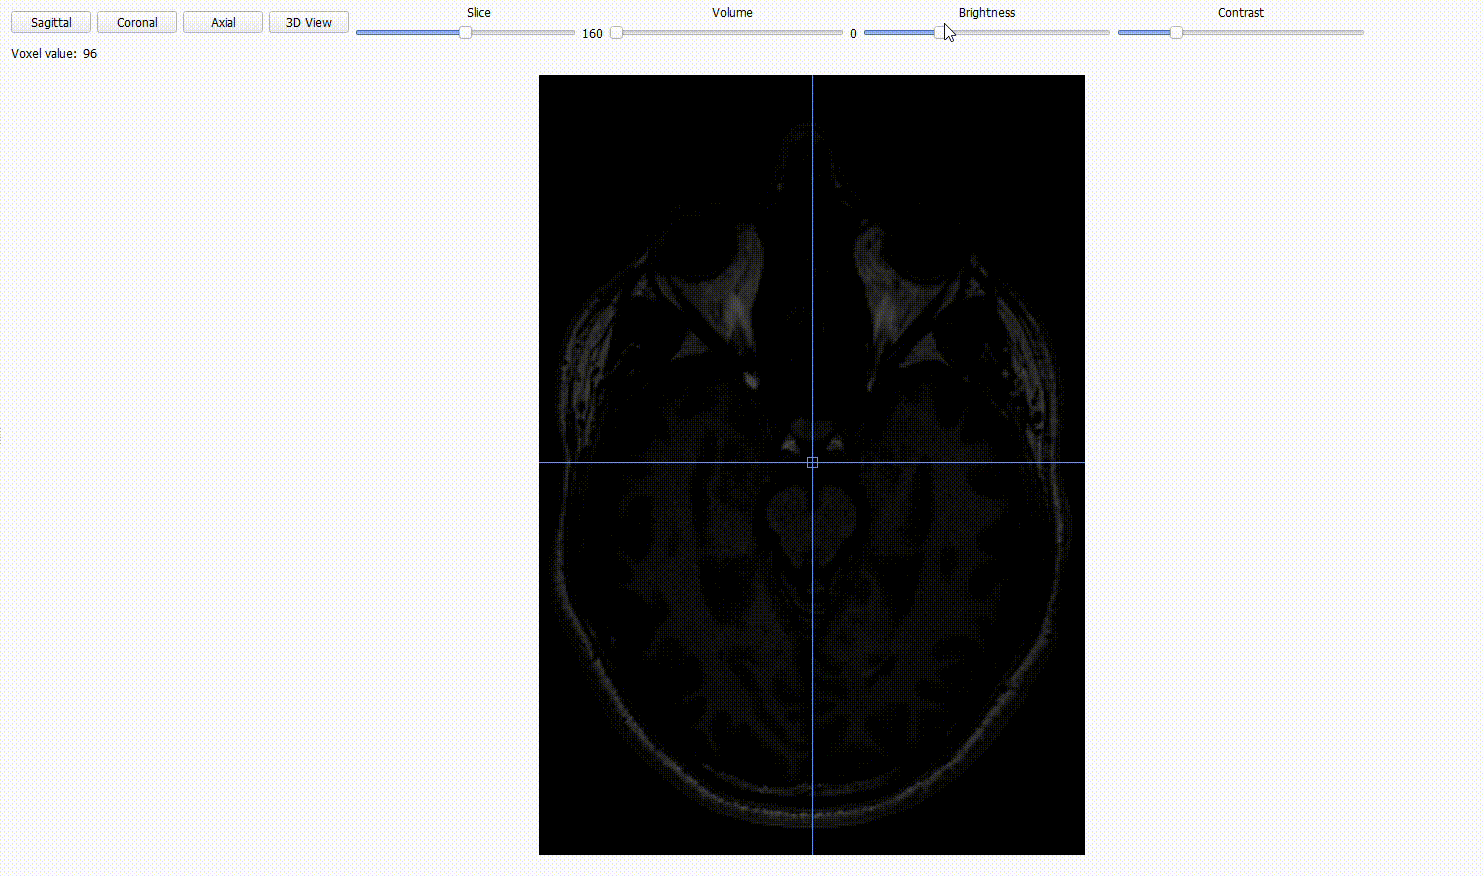

Sequence type view: BIDSplorer can open NIfTI images (.nii/.nii.gz) across different sequence types (anat, func, fmap, dwi). Use the different option to

Inspect the three orthogonal planes with the

Axial,CoronalandSagittalbuttons.

Scroll through the 2D cross-sections of the current plane with the

Slicestoggle.

Adjust

brightnessandcontrastto improve visibility.

For functional (BOLD) images, you can scroll through time using the

volumetoggle.